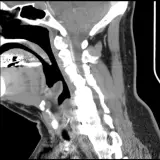

Over 2,100 interactive radiology cases, curated by radiologists for your level of training. Scroll, window, and view cases full screen — just like on PACS. Click linked findings in each writeup to jump straight to them on the image. Cases include sample reports, a focused discussion section, original illustrations, and videos.

完全交互式病例,配备您在 PACS 上期待的各项工具——滚动、调窗、缩放、平移、测量、ROI 和全屏模式。

丰富的标注直接在病例图像上突出关键发现。点击病例讲解中的关联发现,即可跳转至其在扫描上的精确位置。